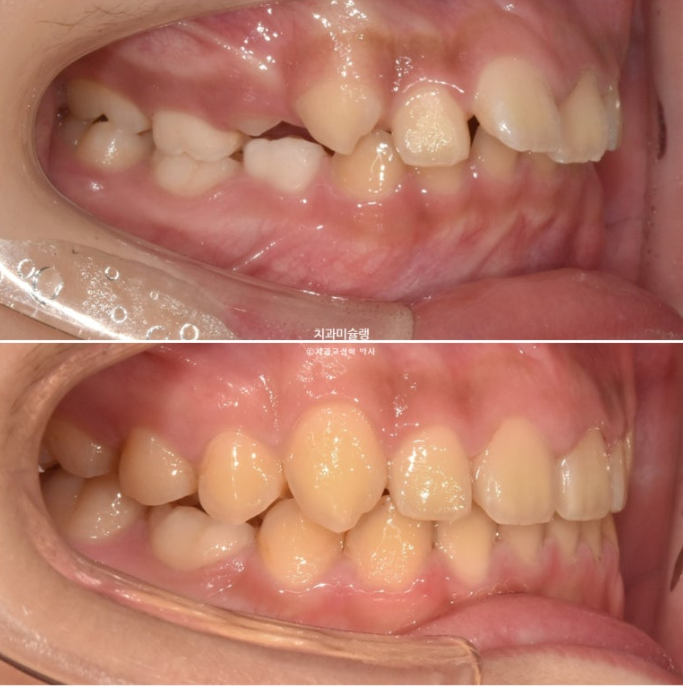

이제 어린이 교정 전후비교 보겠습니다

23.11~25.08

아이의 미소가 달라지고

자신감이 달라집니다.

앞니 뻗침과 돌출 때문에 잘 안 다물어졌던 입이 편하게 다물립니다.